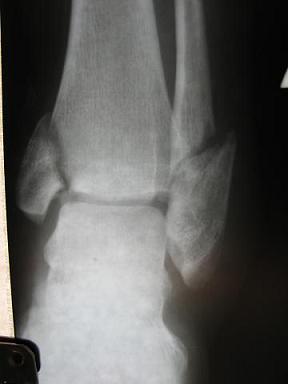

Вложения

pp2.JPG

Так выглядела поломанная "лапка" Светы до гипса

pp2.JPG (14.9 КБ) Просмотров: 7155